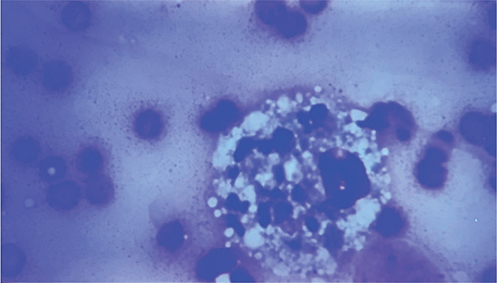

Other conditions causing hemorrhagic vulvar discharge, such as endometritis, trauma, neoplasia of the caudal reproductive tract, urinary infections, foreign bodies or coagulopathies should be ruled out before making a diagnosis of SIPS. Trophoblast cell (Figure 5) can be recovered by vaginal cytology in postpartum dogs with signs of SIPS. Although a normal finding in the early postpartum period, some SIPS patients with clinical signs may have a small number or no trophoblast cells in a vaginal swab.55

Figure 5.

Figure 5. Photomicrograph of vaginal cytology smear (stained with diff quick and visualized under brightfield microscopy at 20 x magnification); note trophoblast cell (white arrow)